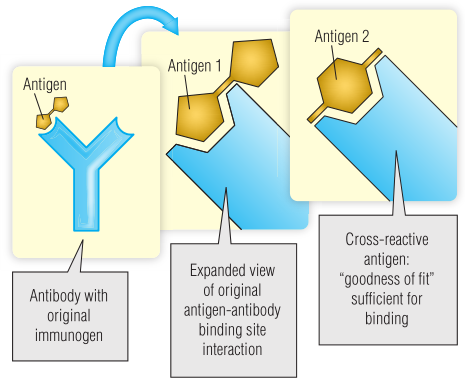

交叉反应性

一种抗体偶尔会与一种以上的抗原结合,这称为交叉反应或多特异性。该抗体是抗原1的特异性抗体,但与另一个分子抗原2,足以产生稳定的结合作用(Fig 5.2)。交叉反应的发生是因为抗原和抗体之间存在足够数量的化学相互作用,以创建一个稳定的结构,而不考虑总的“拟合优度”。值得注意的是,交叉反应可能会产生临床后果(BOX 5.1)。

Fig 5.2 抗体交叉反应示意图